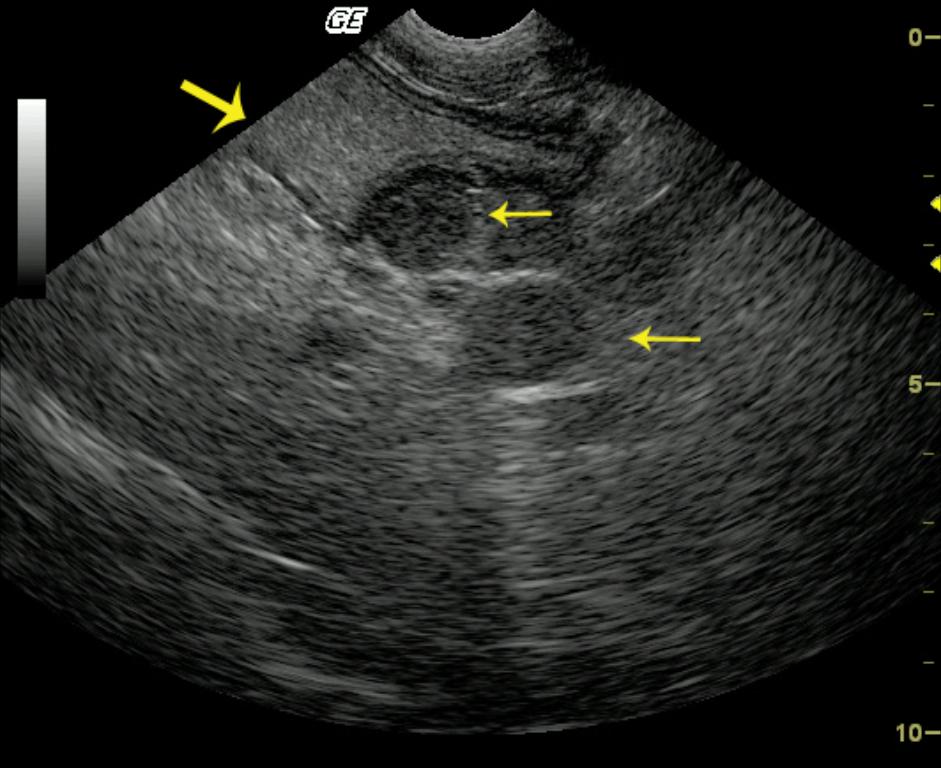

This 10-year-old FS Doberman Pinscher presented for anorexia and weight loss. The physical exam was unremarkable other than mild dehydration and mild cachexia. CBC and blood chemistry analysis demonstrated mild regenerative anemia, moderate leukocytosis with a left shift, mild hypoalbuminemia and hypomagnesemia. The radiographs demonstrate mild ascites with poor organ detail.